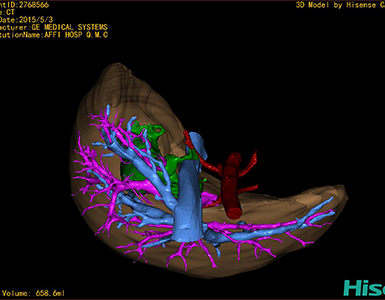

CT结果输入海信CAS系统后行3D重建及手术规划后,于2015-5-6全麻下行“胆总管囊肿切除+胆囊切除+胆总管-空肠吻合术”手术治疗:

术前三维重建及手术方案设计:

将0.625mm双源薄层CT资料的静脉期和动脉期Dicom格式文件导入海信CAS系统。

通过调节窗宽窗位调整CT序号,对肝实质,胆囊,下腔静脉,肿瘤,肝动脉、门静脉及肝静脉等进行三维重建;系统自动计算肝脏体积。

术前手术方案的规划。

术前三维重建:

重建图片